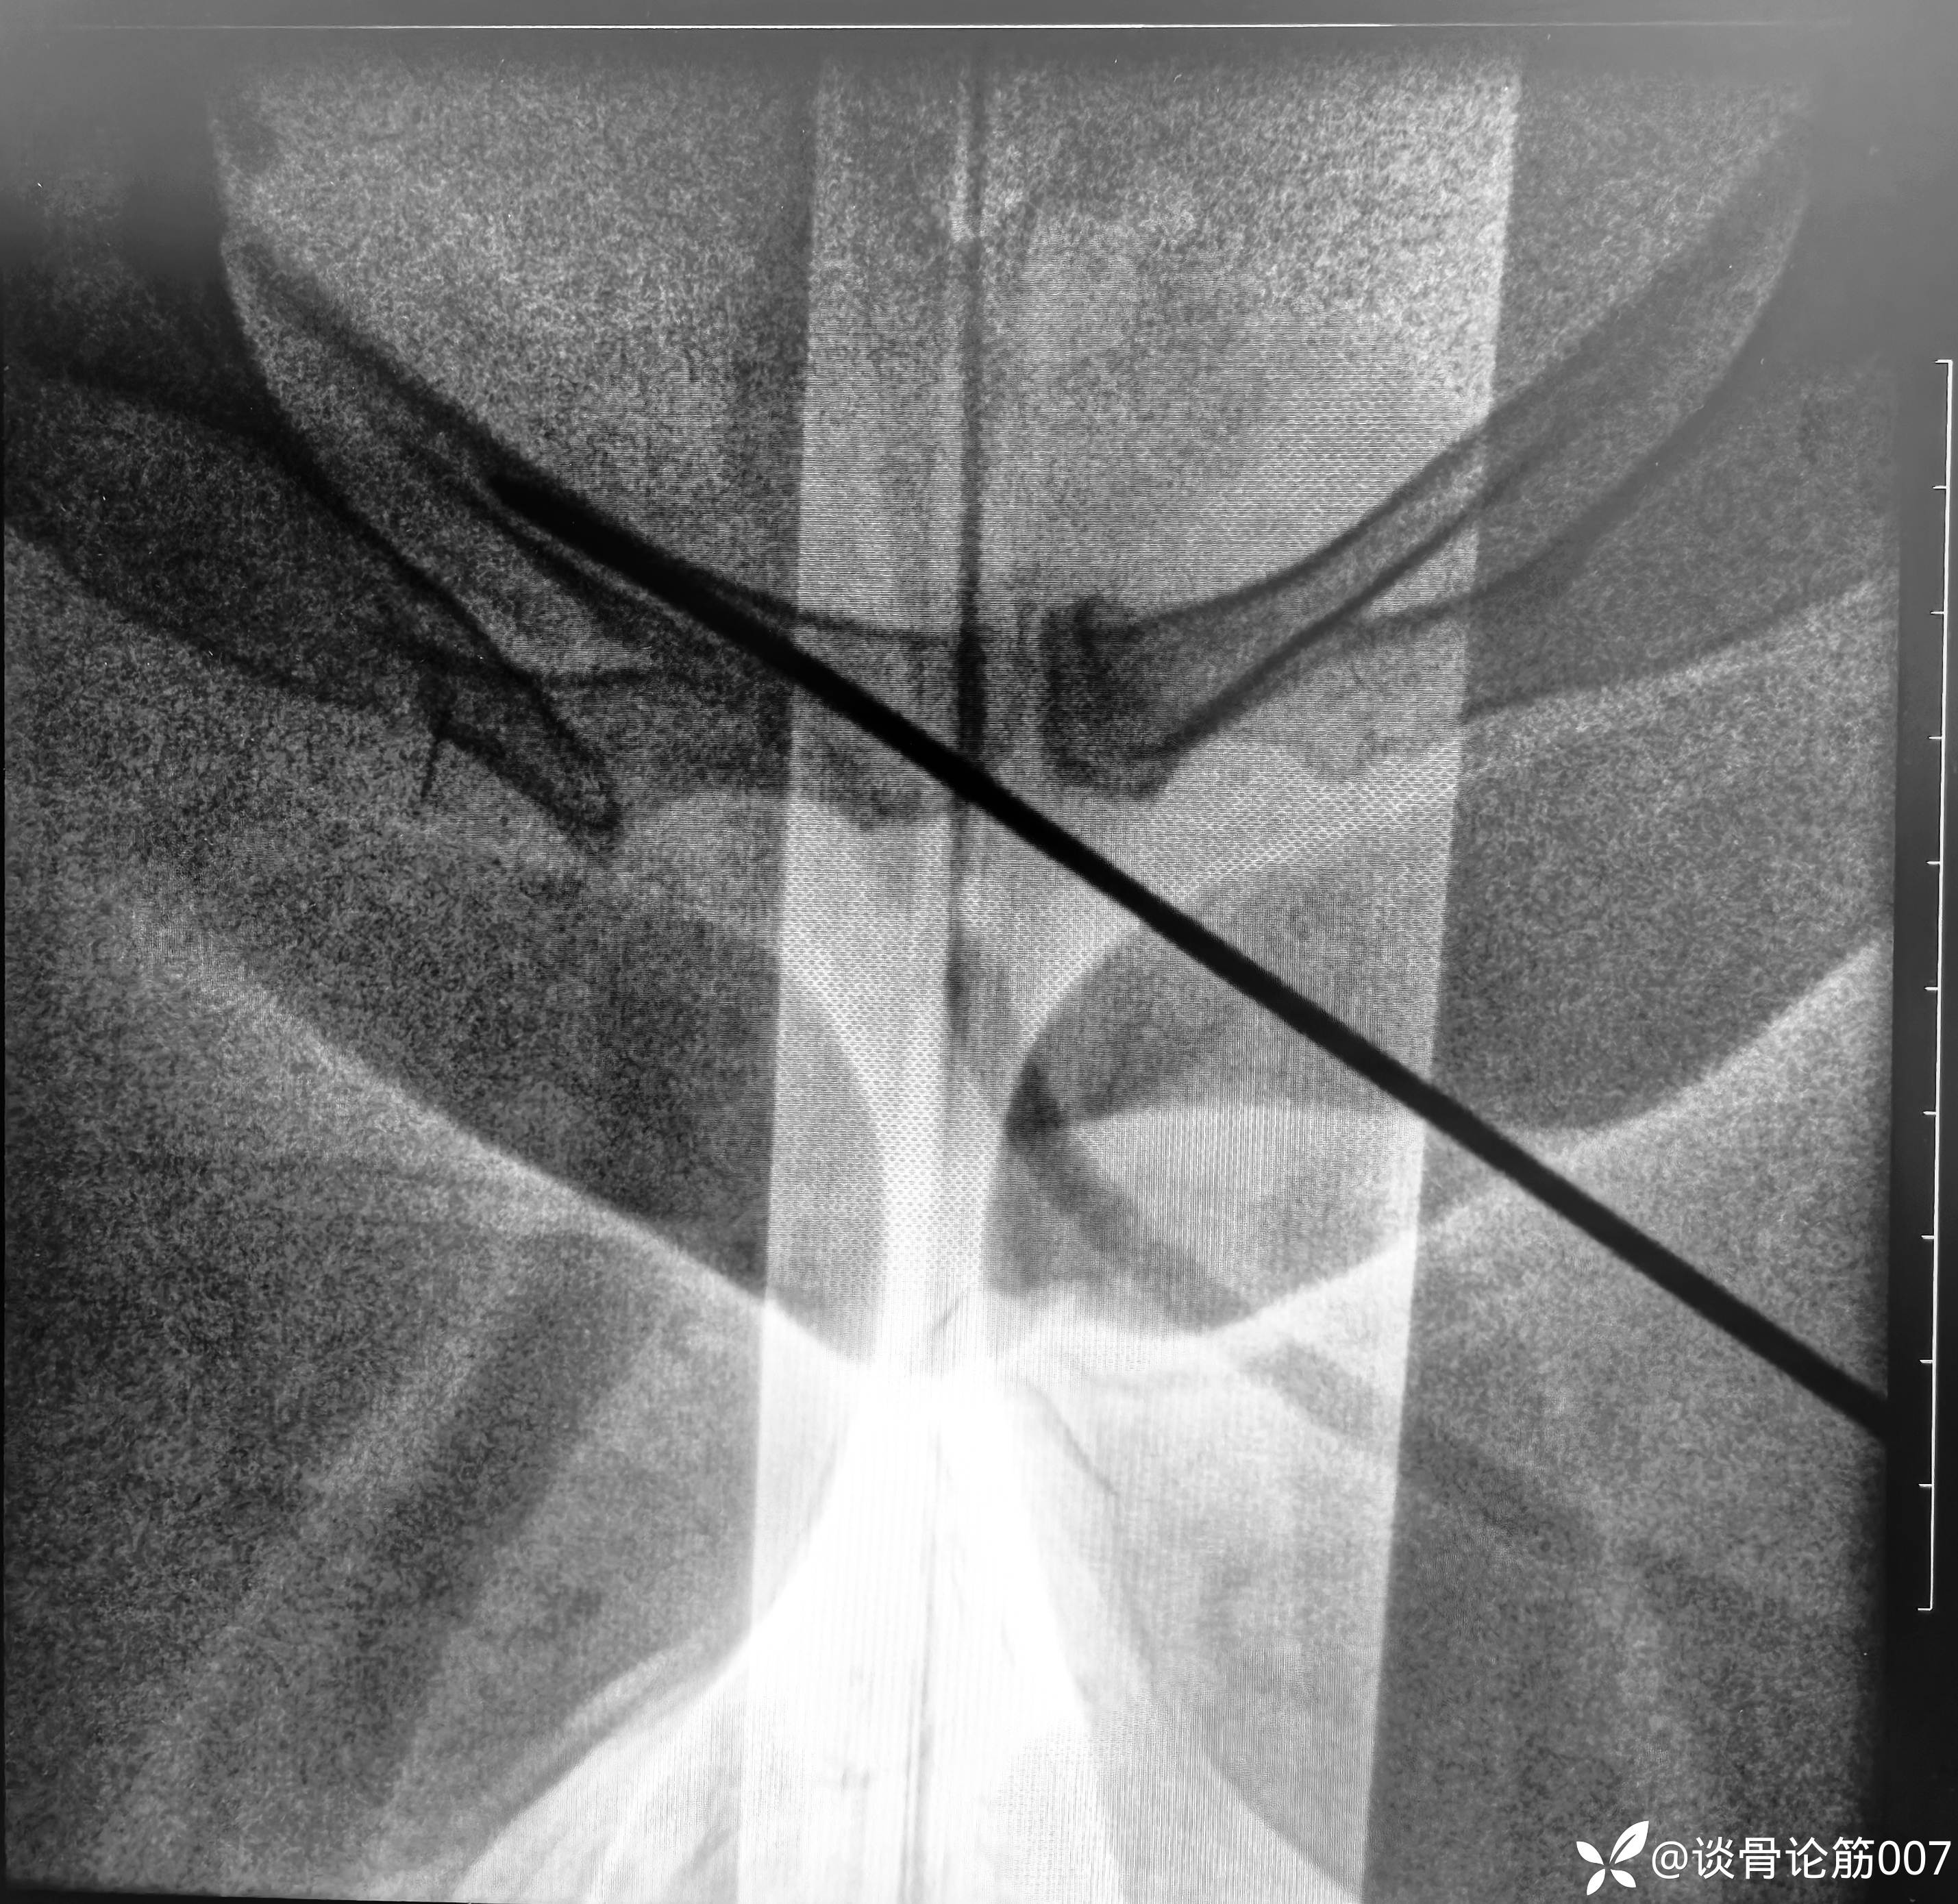

从结果来看,进针点应用粗钢针位置可能刚好一点

女性耻骨上支确实比较细

应用蛇钉技术避开髋臼